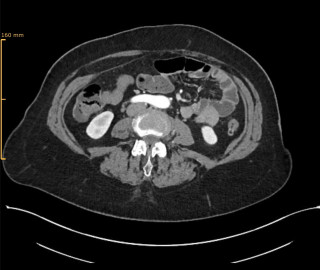

Twenty (n=20) consecutive patients undergoing pancreatic resection were prospectively enrolled. In addition, n=10 patients undergoing other major abdominal surgery served as control group. Dexcom G6 CGM system was used. Time in euglycemic range (TIR) and peak glucose levels were analyzed. Routine serum glucose measurements and daily C-reactive protein (CRP) levels were also assessed. Comprehensive Complication Index (CCI) was used to quantify postoperative complications.

Results

No adverse events related to CGM devices were observed. Glucose levels increased significantly from a median of 7mmol/l (IQR 6-8mmol/l) to 9 mmol/l (IQR 8-1mmol/l, P=0.026) after pancreatic resection. Correspondingly, the TIR decreased from 86.5% (IQR 85-96%) to 78.1% (IQR 34-89%, p=0.042). Perioperative glucose levels (p=0.623) and TIR (p=0.408) remained unchanged in the control group. Linear regression showed a significant correlation between peak glucose levels on day 1, measured by CGM (R=0.738, p=0.004, Figure 1A), and CRP levels on day 2 (R=0.528, p=0.034, Figure 1B) with CCI. In contrast, routine serum glucose levels did not predict complications.

Conclusion

In this pilot study, peak glucose levels on day 1 after pancreatic resection were associated with adverse events. CGM may be a valuable tool to identify patients at risk of complications.